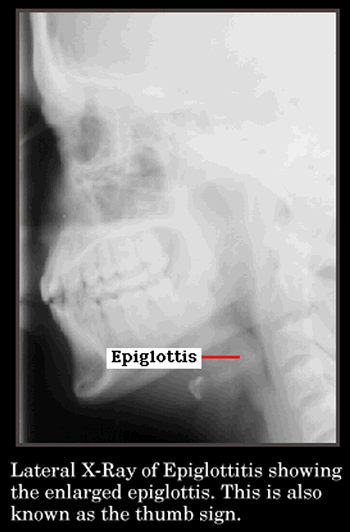

Thumb Sign